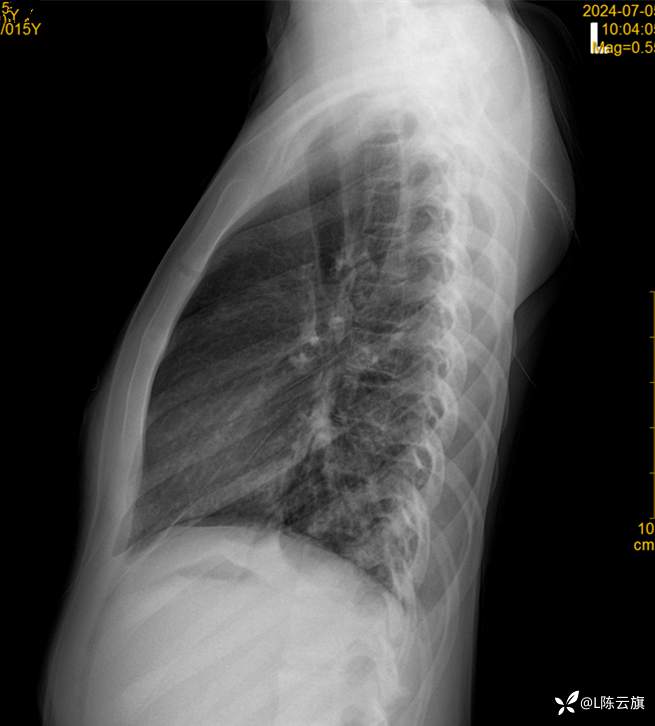

患者女,15岁,精神病住院患者,咳嗽、伴发热两天,余无特殊。